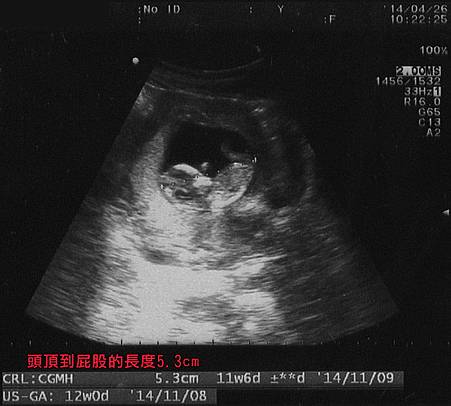

照超波時醫師首先確認寶寶的心跳,也是很快地聽了幾秒,然後說心跳正常。

接著從寶寶上方的角度往下照,要數看看寶寶的雙手跟雙腳有沒有長好,又稍微轉了不同的角度快速看了手腳的樣子。

最後是測量寶寶從頭頂到屁屁的直線長度,也就是寶寶目前的大小。

透過超音波看到寶寶的樣子更像個小人了,胎囊也終於變圓了,不再像之前那樣扁扁的,不過總覺得胎囊還是小了點,寶寶身體整個有點蜷曲在那裏,空間好像不太夠讓寶寶舒服地躺平,也因為這樣曲著身體,測量屁股到頭頂的直線長度感覺應該會不太準確吧? 測量出來的5.3cm我覺得應該是稍微小了一點,但醫師說在正常範圍內。

螢幕上顯示著寶寶現在是11週又6天,明天就正式滿三個月了。